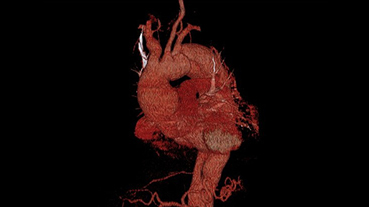

The patient’s severe thrombosis required months of multidisciplinary care and the transplantation of his liver, stomach, large intestine, small intestine, pancreas, and kidney.